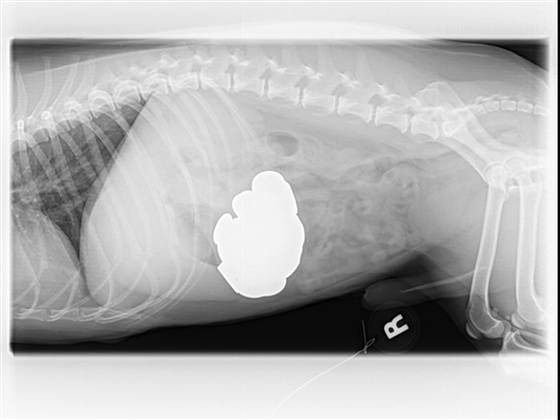

Ένας σκύλος καταβρόχθισε 111 κέρματα

Για να αφαιρεθεί αυτό το ¨μίνι ορυχείο χαλκού ¨ από το ��τομάχι του 13χρονου σκύλου χρειάστηκε εγχείρηση 2 ωρών.

Οι γιατροί που τον εξέτασαν κατάλαβαν τι είχε γίνει από τις ακτινογραφίες που του έβγαλαν και αμέσως το επέβαλαν σε εγχείρηση ,αφαιρώντας 5 κέρματα την φορά για να σώσουν τον σκύλο από τις μεγάλες ποσότητες ψευδαργύρου που θα απελευθερώνονταν και θα κατέστρεφαν σταδιακά το συκώτι και τα νεφρά του.